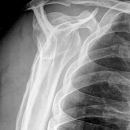

Schulter a.p. (Schultergelenk nach Grashey)

Patient steht mit dem Rücken am Stativ, gesunde Seite um 45° anheben, kranke Seite liegt auf, Arm der aufzunehmenden Seite leicht abgespreizt, Hand in Supination (Handinnenfläche zeigt von der Kassette weg). Kopf zur Gegenseite drehen lassen.

Senkrecht in Gelenkspalt bei Format 18/24.

Bei Format 24/30 oberer Kassettenrand: 2 Querfinger oberhalb der Schulter, prox. Humerus mit in der Einblendung.

Gelenkfläche der Scapulapfanne (Glenoidal-Gelenk) soll strichförmig abgebildet sein, der Humerus soll frei projiziert werden. Die Aufnahme kann mit der Rockwood-Aufnahme kombiniert werden (Röhrenkippung). evtl. Schulterfilter verwenden.

- vollständige überlagerungsfreie Darstellung des Humeruskopfes und des Gelenkes

Bei Fragen im Subacromial-Raum sollte dieser überlagerungsfrei dargestellt werden.